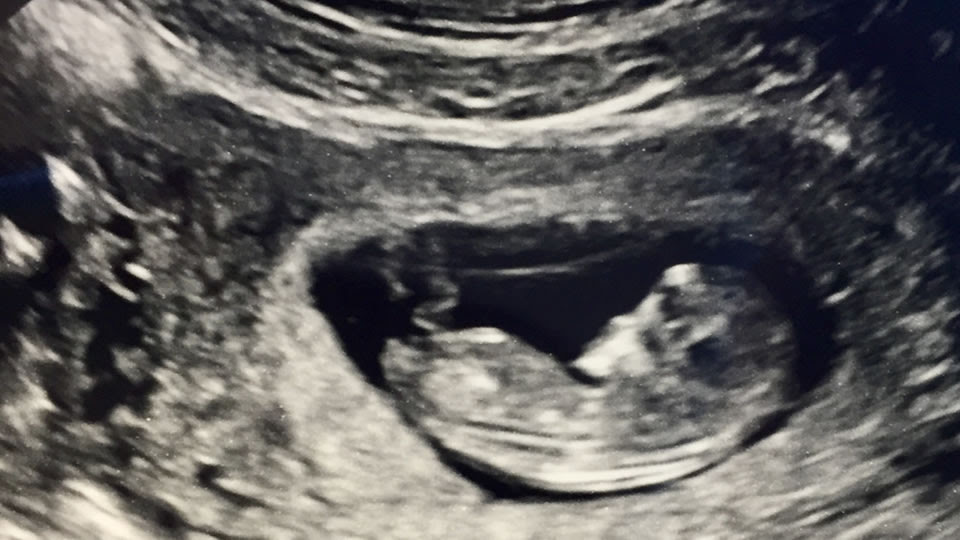

“For you formed my inward parts; you knitted me together in my mother’s womb.  I praise you, for I am fearfully and wonderfully made. Wonderful are your works; my soul knows it very well.” –Psalm 139:13-14 (ESV) Dear Friends: This week marks the 45-year anniversary of legalized abortion in American following the U.S. Supreme Court’s 1973 ruling